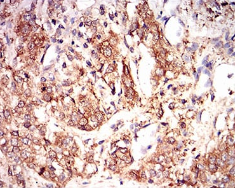

| AC2131 | EIF2A Mouse Monoclonal antibody[3A711] | 100ug | $367 | 10days |

| AC2131 | EIF2A Mouse Monoclonal antibody[3A711] | 200ug | $660.6 | 10days |